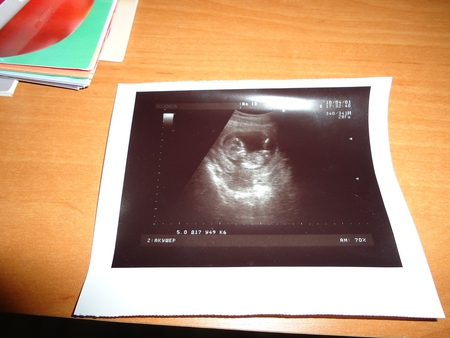

Результаты: УЗИ, КТГ, доплера, скринингаСрок поставили 13-14 неделек, малыш 72 мм, сердечко 140 ударов в минуту. Когда узистка включила звук сердце послушать у меня аж мурашки побежали, посмотрела в монитор, а там такая кроха))))) Попыталась сфоткать фото но получилось не очень удачно, без вспышки не видно, а с вспышкой искажает... Ну вот:

Здесь такое ощущение что ножку вверх поднял))) Узиска показала как он ручками шевелил)))